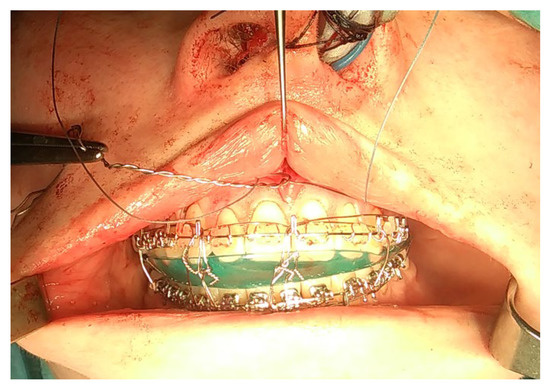

- A condylectomy with BSSO and Lefort I simultaneously was described by Wolford in 2002; however, some authors report operated TMJ joint instability, which might be related to the degree of excised bone and poor condyle stabilization with at least lateral pterygoid muscle reattachment or other, perhaps even related with IMF intramaxillary fixation devices to stabilize the occlusion [75] (Figure 9);

- (7)